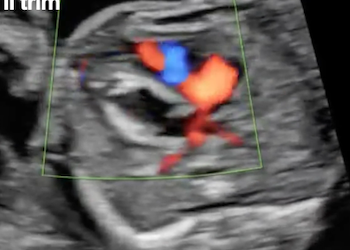

How To Do Agosto 2021: Cesarean Scar Pregnancy

Cari soci, questo mese un nuovo video "How to do", sulla diagnosi ecografica di gravidanza su cicatrice di pregresso taglio...